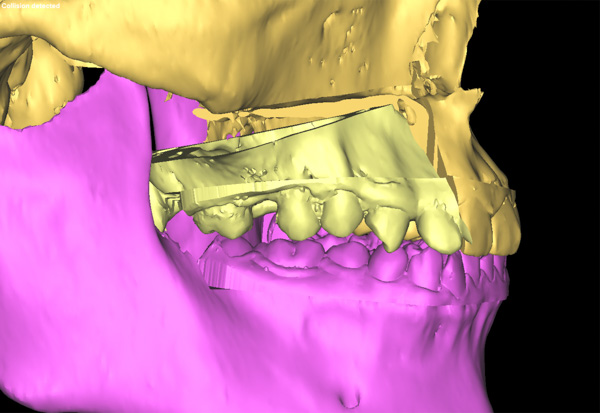

頜面畸形帶給患者心理的痛苦是非常嚴(yán)重的,再加上患者正處在最美好的人生階段,所以手術(shù)只許成功,不許失敗,所有的環(huán)節(jié)必須容不得一絲差錯(cuò)。為了能使上頜骨能精確地移動(dòng),口腔科專家采用了先進(jìn)的3D模擬技術(shù)制作出了咬合導(dǎo)板,在術(shù)前多次模擬重建手術(shù),并向患者展示手術(shù)過(guò)程,使手術(shù)過(guò)程達(dá)到了最大可能的精準(zhǔn),減輕患者的心理負(fù)擔(dān)。

手術(shù)當(dāng)天,口腔科手術(shù)團(tuán)隊(duì)首先按照術(shù)前設(shè)計(jì)并3D模擬的截骨導(dǎo)板對(duì)右側(cè)上頜骨進(jìn)行精準(zhǔn)分離,按照術(shù)前設(shè)計(jì)的咬合導(dǎo)板精確移動(dòng)上頜骨達(dá)到預(yù)定位點(diǎn),最后精準(zhǔn)的使用堅(jiān)強(qiáng)內(nèi)固定固位。經(jīng)過(guò)4個(gè)小時(shí)的努力,完成了正頜手術(shù),待拆除鈦板后即可進(jìn)行咬合關(guān)系和對(duì)稱面型治療。